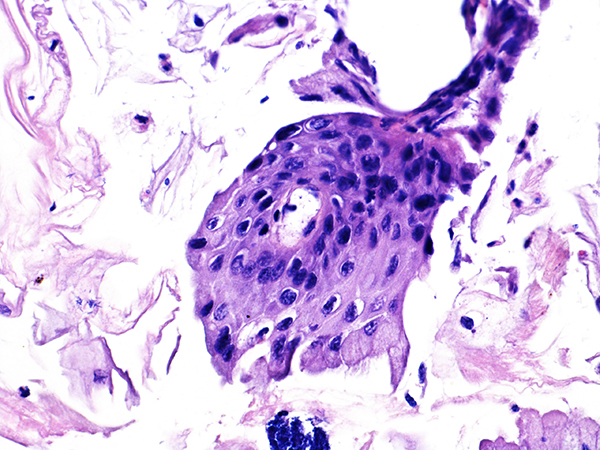

Case 1

Area 1 - Soft Bx CIN 2

40x - High Power